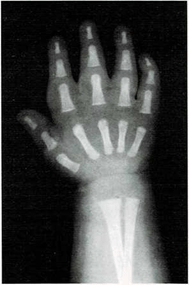

Mi madre me respondió: “Una razón de que lo encuentres blando es que sus huesos no son tan duros como los tuyos. Los niños, al nacer, tienen muy pocos huesos duros. Los huesos de su esqueleto se componen sobre todo de cartílago. Pero las células óseas trabajan sin descanso, y por ello sus huesos crecen y se endurecen muy deprisa. Tus huesos son más largos y duros que los del niño. Los huesos seguirán creciendo y se endurecerán hasta tus veinte años.

El médico me respondió: “Tu muñeca tiene ocho huesos. Pero no todos crecen a la vez. Los huesos de la muñeca de algunos niños crecen más deprisa o más despacio que los de otros niños. Pero los huesos de la muñeca crecen a un mismo ritmo en todos los niños sanos. Si los huesos de tu muñeca salen bien en la radiografía, quiere decir que el resto de los huesos de tu cuerpo también están bien.”

En ella ya se ven claramente los ocho huesos.